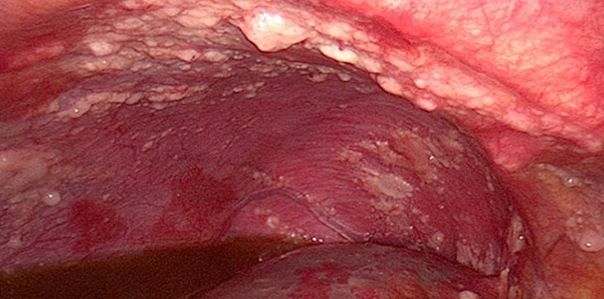

Karın içi organları kaplayan ince bir tabaka olan karın zarının (peritonun) kötü huylu tümör hücreleri tarafından tutulmasına ya da etkilenmesine peritoneal karsinomatozis yani karın zarı kanseri denir. Genellikle ileri evrelerde teşhis edilen bu kanser türü başka bir kanserin karın zarına yayılması sonucu oluşur. Ancak nadiren başka sebebe bağlı olmayan primer periton kanseri de olabilir.

Karın zarı kanserinin nedeni tam bilinmese de, periton hücrelerinde oluşan mutasyonla kontrol dışı büyümeyle kanser başlamaktadır. Peritoneal karsinomatozis daima ilerlemiş kanser hastalığının bir göstergesidir ve belirgin olarak azalmış yaşam beklentisi ile beraber seyreder. Peritonun tümöral tutulumu ciddi bir tıbbi tedavi sorunu oluşturmaktadır çünkü tedavisi zor hatta imkansızdır. Periton içerisine yerleşmiş olan tümör hücreleri peritonun açıklıklarından bütün peritona ve altındaki organlara yayılabilir. Peritoneal karsinomatozis  olan kişilerde karın zarı etkilendiği için karında yoğun su birikmesi görülür. Peritoneal karsinomatozis bebeklerde ve çocuklarda çok nadirdir ama bazı çocukluk çağı kanserlerinde de görülebilir.